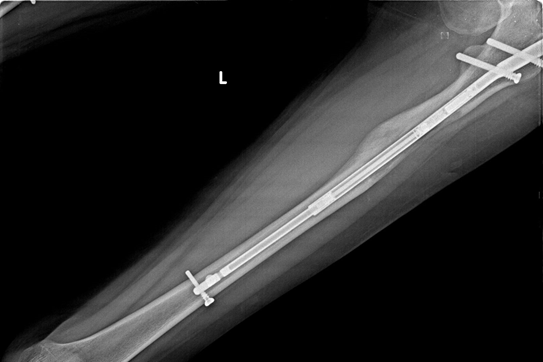

Intramedüller Çivi

Precice Max bileşeni intramedüller çivi boy uzatma ameliyatı ya da benzeri ortopedik ameliyatlar esnasında hastaların deneyimini zenginleştirmek amacıyla geliştirilmiş son teknoloji bir ürün özelliği gösteriyor. Ana malzemesinin titanyum olduğu biliniyor. Titanyum çivi Precice Max yönteminin alametifarikası kabul ediliyor. Titanyum biyouyumlu yapısı ve yüksek direnciyle kemik içine yerleştirildiğinde çok daha etkili bir performans sergiliyor. Farklı çaplarda geliştirilen titanyum çiviler hastaların kemik yapısına göre tercih ediliyor. Titanyum çiviler dayanıklı olmasının yanı sıra fazlasıyla hafif tasarıma sahip.

Precice Max yönteminde kullanılan titanyum çiviler 10 mm, 11,5 mm, 13 mm ve 14 mm boyutlarda üretiliyor. Hastada hangisinin kullanılacağı yapılacak detaylı muayene sonucunda hastaya özel belirleniyor. Çivinin boyutları yük taşıma kapasitesini temsil ediyor. Boy uzatma operasyonu esnasında kullanılan çiviler uzaktan kumanda sistemi ile yönetiliyor.